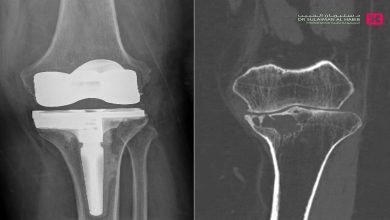

مستشفى الدكتور سليمان الحبيب بالفيحاء في جدة يجري جراحة معقدة لاستئصال ورم واستبدال مفصل الركبة لأربعينية

أجرى مستشفى الدكتور سليمان الحبيب بالفيحاء في جدة، عملية معقدة لاستئصال ورم دموي واستبدال مفصل الركبة، لمراجعة تبلغ من العمر…